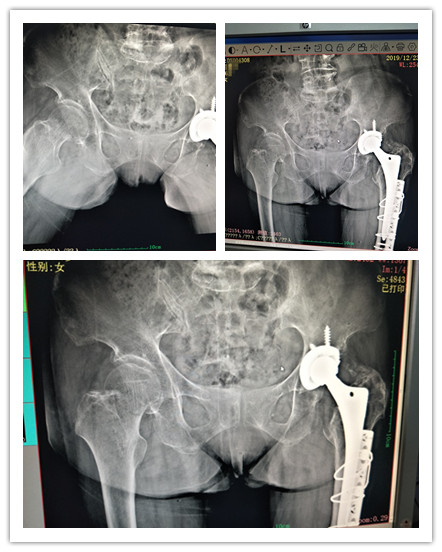

66岁患者何女士在行走时不慎摔倒,当即右髋部疼痛,活动受限18小时入广州东仁医院治疗。外二科专家对其病史进行了详细采集,了解到患者约6年前于它院行左侧人工全髋关节置换术,约5年前出现血压偏高,家人诉最高收缩压170mmhg,未给予诊察治疗。查体:右下肢呈屈膝屈髋畸形,髋部触痛明显,可触及轻度骨擦感,右髋主动活动受限。经辅助检查DR示:右股骨颈骨折。2、左髋人工全髋关节置换术后改变,腰2-腰5椎体陈旧性压缩性骨折。诊断:1、右股骨颈骨折。2、左髋人工全髋关节置换术后,3、腰2-腰5椎体陈旧性压缩性骨折。4、原发性高血压。5、老年痴呆症。

经专家团队综合评估病情且仔细制定方案后,为患者成功实施了右髋关节人工关节置换术,成功解决了患者疼痛及关节功能问题,一句“谢谢”承载患者无尽的感激。